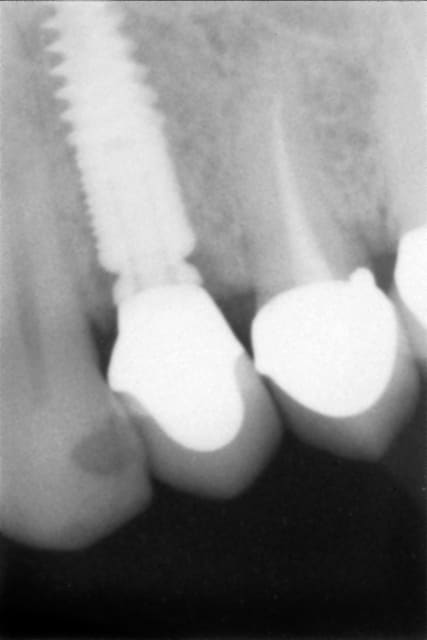

Alors voilà le premier cas :

EII sur 24 du 16/09/10

Obtention d'une stabilité primaire, mais plutôt fragile.

Temporisation par bridge Maryland collé sur une couronne métal en distal, ce qui a été la cause de multiple descellements, et possible traumatismes de l'implant via sa vis de cicat.

Manifestement une autre cause possible est la présence d'une infection maousse en dans le site le jour de la pose...

Qui dit la faute à Tekka ?